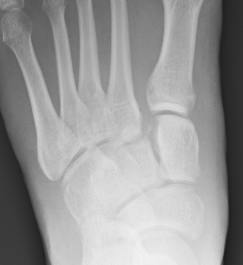

1. Diastasis of the intermetatarsal gap between the 1st and 2nd metatarsals

2. Widening of the space between the medial cuneiform and base of 2nd metatarsal

3. Second metatarsal Fleck sign - avulsion of Lisfranc ligament from base of 2nd metatarsal

4. Widening of inter-cuneiform distance

5. Dorsal subluxation of the metatarsals

6. Tarsometatarsal alignment disruption

- medial border 1st metatarsal aligns with medial border medial cuneirform (AP foot)

- medial border 2nd metatarsal aligns with medial border middle cuneiform (AP foot)

- medial border 3rd metatarsal aligns with medial border lateral cuneiform (AP view)

- medial border 4th metatarsal aligns with medial border of the cuboid (oblique view)